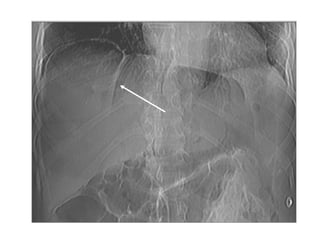

HÔI NAÈM NGOAØI LOØNG OÁNG

TIEÂU HOÙA

• Traøn khí töï do trong oå buïng

• Hôi sau phuùc maïc (caû trong heä nieäu)

• Hôi trong tónh maïch cöûa, ñöôøng maät

• Hôi trong thaønh moät taïng: oáng tieâu hoaù, tuùi maät

• Hôi trong oå asbess (oå buïng hoaëc trong taïng)

Hơi trong đường mật trong gan

Hơi trong thành và trong lòng túi mật

Tuï khí sau phuùc maïc

sau sinh thieát